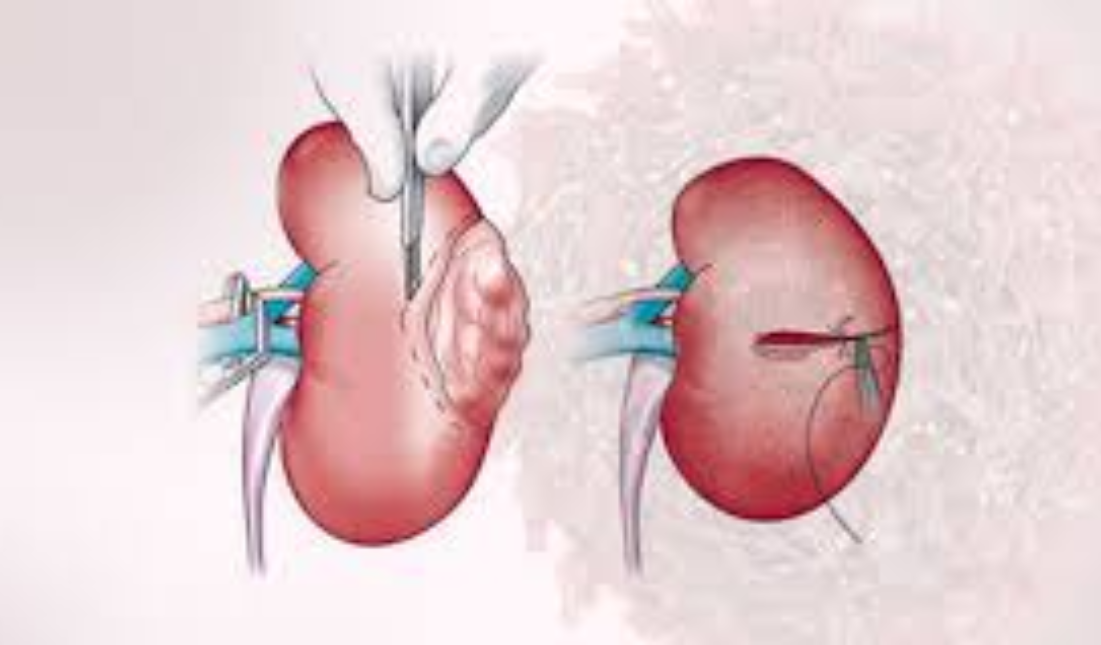

Early Detection of Pancreatic Cancer: Why Surgery Offers the Best Chance of Cure

Home Pancreatic cancer is not very common in India, but it is...